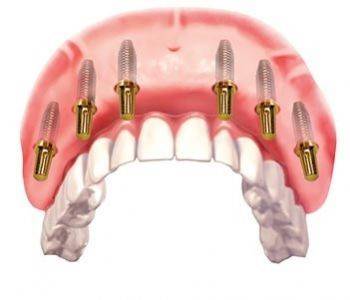

什么是MINI种植体

Mini种植体是一种直径比常规种植体小很多的特殊植体,它是用于活动义齿的修复中,要比传统的义齿修复更加稳定。

传统种植体和MINI种植体之间有什么不同?

Mini种植体允许牙医不用在牙龈上切口直接植入,术后手术痛苦减少,且可以进行即刻修复

目前新加坡有两种植牙技术,一种是迷你植牙,用细小的螺丝来固定牙齿,直径只有约两毫米。

相反的,迷你植牙只需几天,价格是传统植牙的一半。

迷你植牙,它是一种伤口小的微创手术。一些80岁以上的病人,不适合做传统植牙,因为骨头厚度不够,但可利用迷你植牙,帮他们植牙,改变他们的生活。

只有一些情况适合做迷你植牙,比如用来植入下巴较小的前牙或固定松脱的全副假牙,也可用来暂时支撑牙桥。